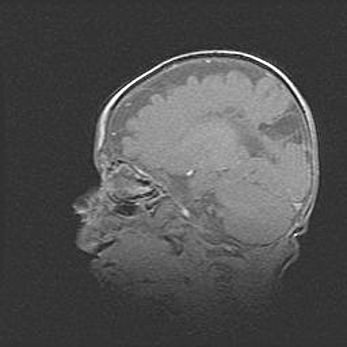

Церебральная ишемия II.

Возраст: 5 дней

Вес: 3400 г

Пол: женский

Окружность головы: 35 см

Срок гестации: 39 недель

Церебральная ишемия – это заболевание, характеризующееся недостаточностью (гипоксией) либо полным прекращением (аноксией) снабжения мозга кислородом по причине закупорки одного или нескольких сосудов. Это приводит к  что метаболическим расстройствам различной степени тяжести в тканях головного мозга, развитию коагуляционных некрозов и гибели нейронов.